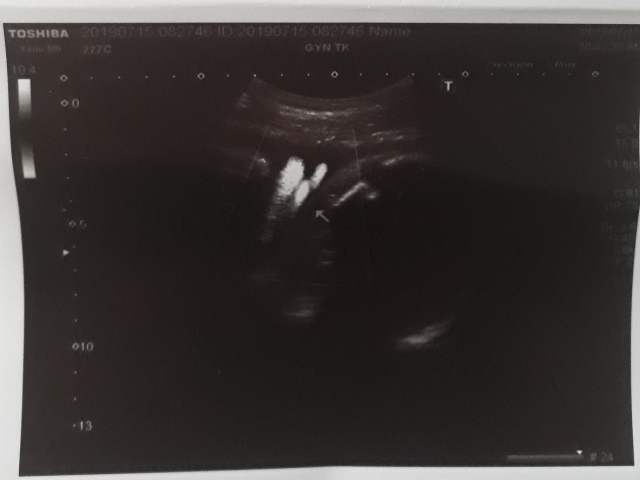

| 仙人掌(2019/07/15)的真心話 星期一 天氣晴 編號19-185 |

29週又3天↓